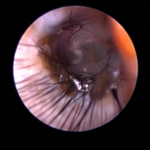

フレンチブルドックはアトピー性皮膚炎、食物アレルギー、脂漏症、甲状腺機能低下症など皮膚病になりやすい犬種です。さらにフレンチブルドックの耳道はもともと入口がとても広く、鼓膜手前で極端に狭くなっています。もし、これらの皮膚病を発症すると外耳炎が起こりやすくなります。外耳炎が起こると耳垢が溜まり、耳洗浄による耳道刺激があったり、微生物の増殖など負のサイクルに陥ることがあります。さらに耳道周囲の体毛が耳の中に入りやすいため、鼓膜手前に毛が蓄積します(写真)。体毛、微生物が増殖した耳垢、皮膚病の放置といった悪化因子が重なると非常に重度の中耳炎になります。

さらにフレンチブルドックの初期の中耳炎の症状にはなかなか気付けないことが多いです。このことも病気を進行させる大きな要因になっています。皮膚病が治療されていないフレンチブルドックは耳の病気に要注意です。